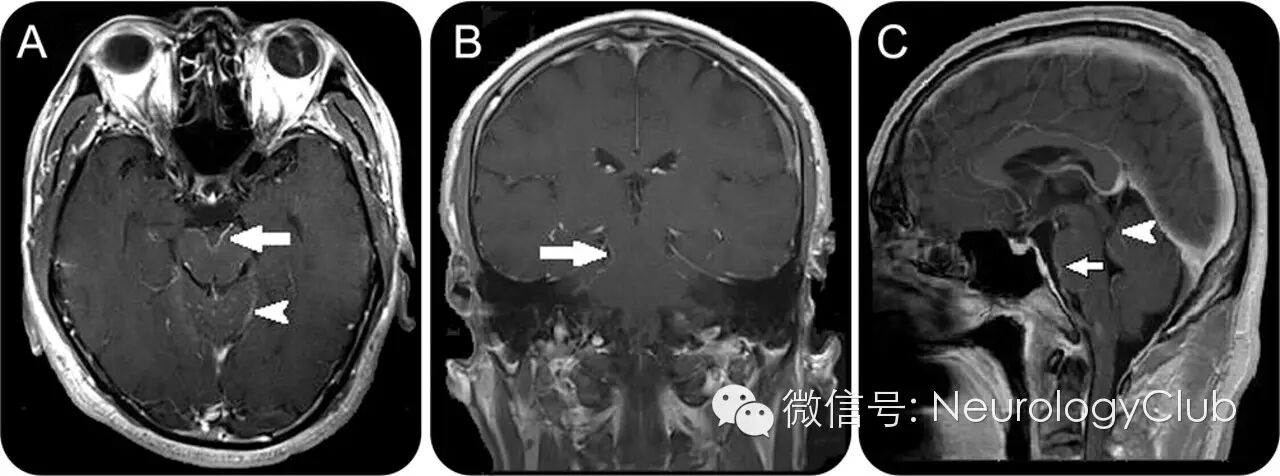

(增强MRI提示中脑,腹侧脑桥和小脑软脑膜强化)

VKHS合并颅内缺血性病灶。a-b:FLAIR;c:DWI;d:ADC;e-f:MRA